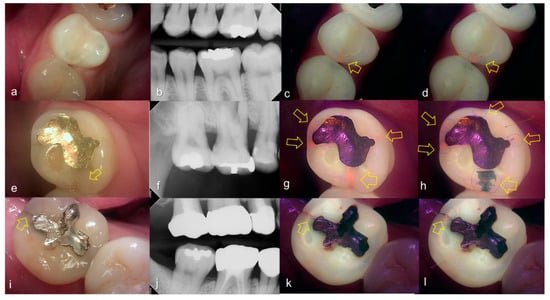

Evaluating proximal dental caries according to the QLF criteria and X-ray criteria, moderate positive correlation was observed (r = 0.63, p < 0.0001). Among the QLF parameters classified based on X-ray criteria, the |ΔFmax| value increased significantly as the score value increased from 1 to 4 (from 3.12 to 19.56). In particular, |ΔFmax| was about 5.7-fold higher for proximal dental caries score = 3 (17.64) than proximal dental caries score = 0 (3.12), and the maximum loss of fluorescence was 6.3-fold higher for the proximal dental caries score = 4 (19.56) (Table 2). The cut-off value of |ΔFmax| for detecting proximal dental caries (X-ray criteria scores 0 and 1 vs 2–4) was 5.95. The sensitivity, specificity and AUROC of parameter were 0.74, 0.73 and 0.81, respectively. However, the sensitivity, specificity and AUROC of the parameter ΔRmax were 0.83, 0.00 and 0.59 (Table 3). Representative images of QLF and bitewing radiograph of proximal dental caries are shown in Figure 6, Figure 7 and Figure 8.

Figure 6.

Proximal dental caries: (a–d) QLF caries score 0 (no fluorescence loss and no red fluorescence increase in occlusal surface (distal side)) and radiographic caries score 1 (radiolucency visible in the enamel) on #14 and QLF caries score 0 (no fluorescence loss and no red fluorescence increase in occlusal surface (mesial side)) and radiographic caries score 2 (radiolucency in the dentine but restricted to the outer 1/3 of the dentine) on #15; (e–h) QLF caries score 1 (fluorescence loss and red fluorescence present in occlusal surface (distal side)) and radiographic caries score 2 (radiolucency in the dentine but restricted to the outer 1/3 of the dentine) on #14 and QLF caries score 0 (no fluorescence loss and no red fluorescence increase in occlusal surface (distal side)) and radiographic caries score 2 (radiolucency in the dentine but restricted to the outer 1/3 of the dentine) on #15; (a,e): white-light image of QLF; (b,f): fluorescence image of QLF; (c,g): bitewing radiograph; (d,h): analyzed QLF image using QA2 software.

Figure 7.

Proximal dental caries: (a–d) QLF caries score 0 (no fluorescence loss and no red fluorescence increase in occlusal surface (distal side)) and radiographic caries score 3 (radiolucency extending to the middle 1/3 of the dentine) on #16; (e–h) QLF caries score 2 (fluorescence loss and red fluorescence glow extending around occlusal surface (distal side)) and radiographic caries score 3 (radiolucency extending to the middle 1/3 of the dentine) on #14; (i–l) QLF caries score 2 (fluorescence loss and red fluorescence glow extending around occlusal surface (distal side)) and radiographic caries score 3 (radiolucency extending to the middle 1/3 of the dentine) on #15; (a,e,i): white-light image of QLF; (b,f,j): fluorescence image of QLF; (c,g,k): bitewing radiograph; (d,h,l): analyzed QLF image using QA2 software.